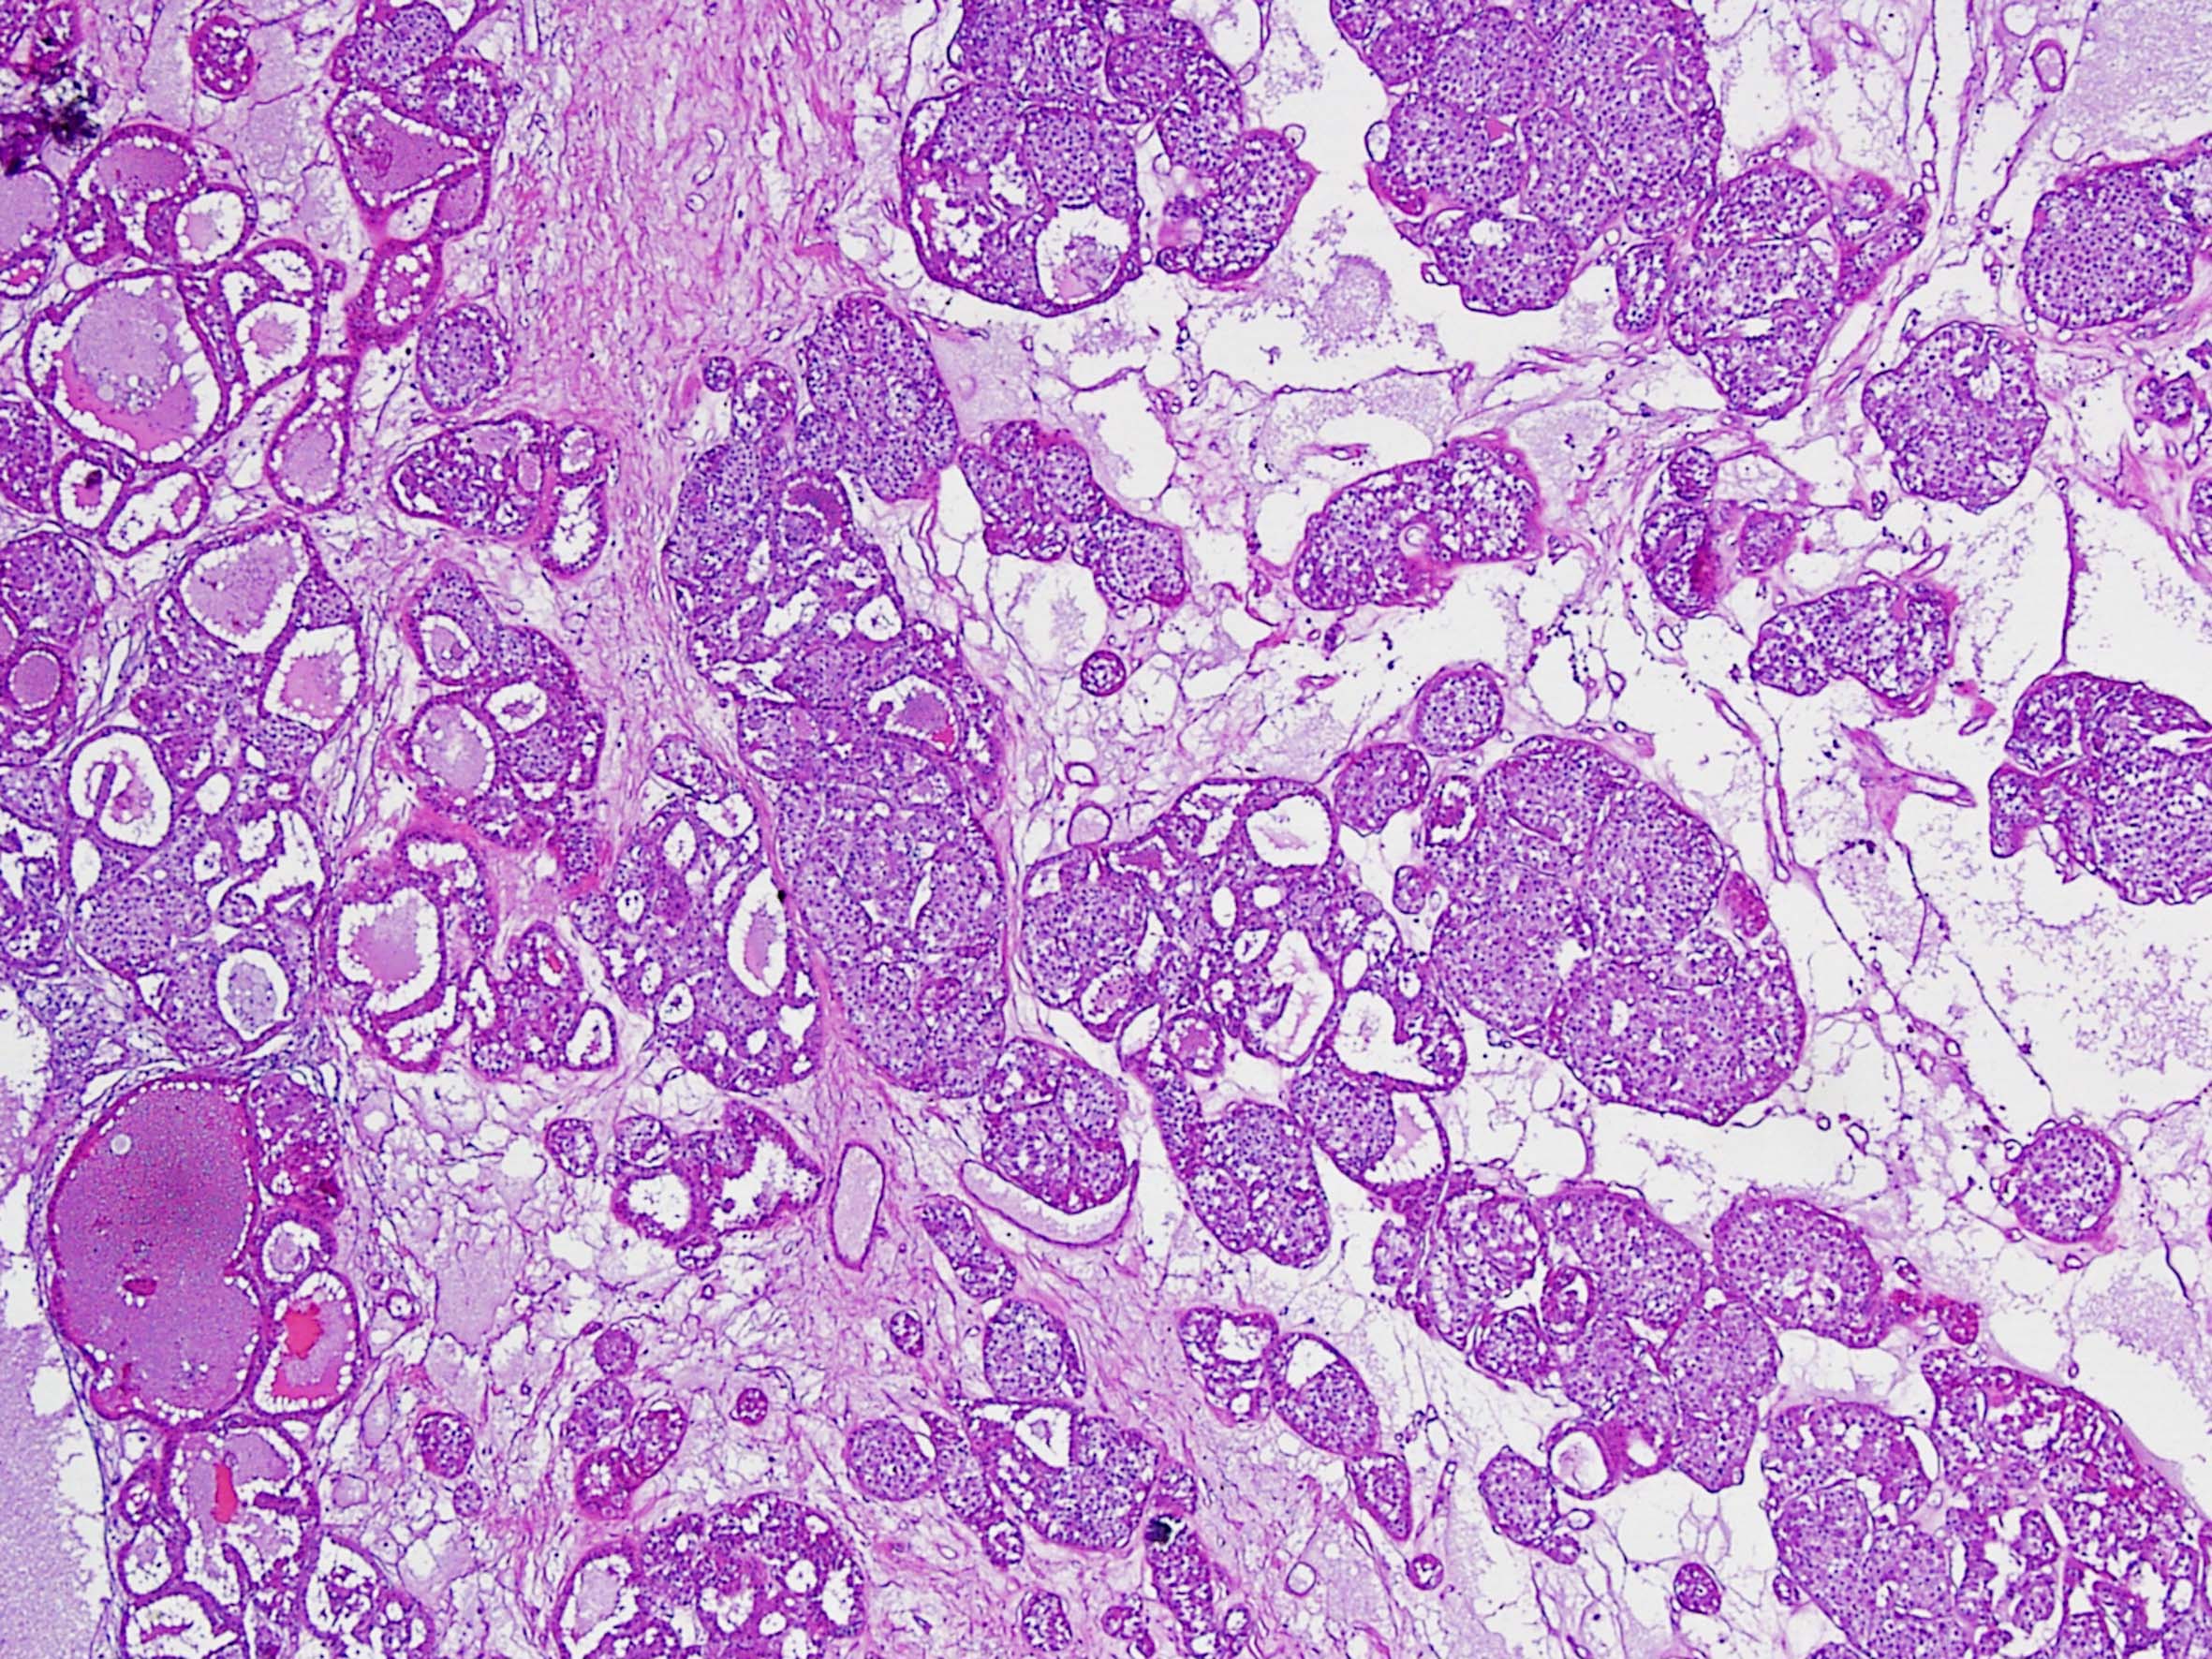

Renal tumor grading

Case ID: 290